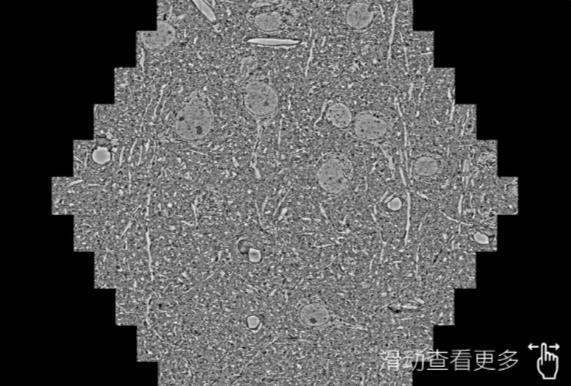

鼠腦切片。左圖使用蔡司掃描電鏡MultiSEM706對165μmx143pm麵積區域成像,耗時僅需1.5秒。右圖為鼠腦切片中30μm區域放大效果。樣品由芝加哥大學B.Kasthuri提供。

使用蔡司高速掃描電鏡MultiSEM對1mm²人腦皮層組織進行高分辨成像,並對其中的各種細胞結構進行三維重構分析。左圖展示了2x3mm²組織平麵中錐體神經元的三維重構效果。右圖顯示了局部體積神經元三維重構。圖像由哈佛大學chtman實驗室提供,渲染圖由D. Berger 製作。